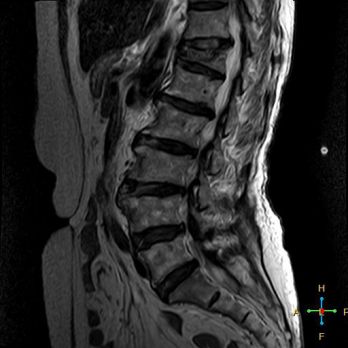

——良性压缩性骨折MR信号特点—— 良性骨折的修复过程:缺血性变化--修复(骨髓水肿、血流增加或充血现象)--修复近完成(血流恢复正常)--慢性期(脂肪组织再生)。 正常成人:椎体为黄骨髓,T1WI 、T2WI 均为高信号。 当骨髓内出现水肿时,T1 低信号, 与残余的正常骨髓形成明显对比,所以椎体压缩骨折后,MR 信号改变以 T1WI 上观察最好;而在常规 T2WI 图像上,病变骨髓的长 T2 高信号与正常骨髓脂肪信号差别较小,不易观察;T2WI 脂肪抑制技术对于突出显示骨折区长 T2 组织信号具有独特优势,对于判断椎体是否发生脂肪变及骨折是否愈合也有一定价值。 急性早期,椎体压缩,局部缺血,骨髓水肿,T1WI 不均匀低信号,T2WI 高信号,增强扫描无明显的强化。 随后,骨折部位开始修复,血流量增加,增强扫描可出现明显的强化,平扫信号无改变。 慢性期,骨髓内脂肪组织再生,T1WI 椎体内呈混杂高信号。

由于大多数外力轻微,椎体内多形成范围局限、移位不明显的骨折线,骨折线周围水肿亦多局限,因此,较少出现全椎体信号异常。

椎体后角回避现象:T1WI 椎体上部或大部呈低信号, 而后角信号不变。

4 总结:鉴别诊断 ——良性压缩性骨折—— 楔形或凹陷形 连续性分布 椎间盘增厚双凸状,许莫氏结节 急性期T1WI不均匀低信号 椎体后角翘起突入椎管内 椎体后角回避现象 可伴椎弓根水肿、无膨大 椎旁薄环形软组织影